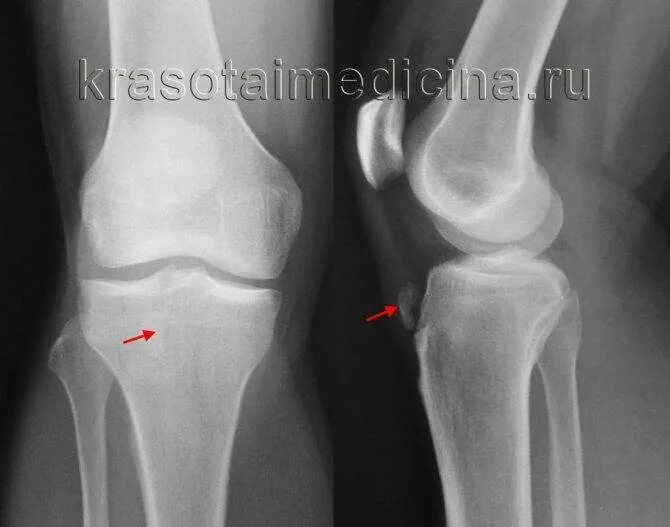

Болезнь осгут шляттера